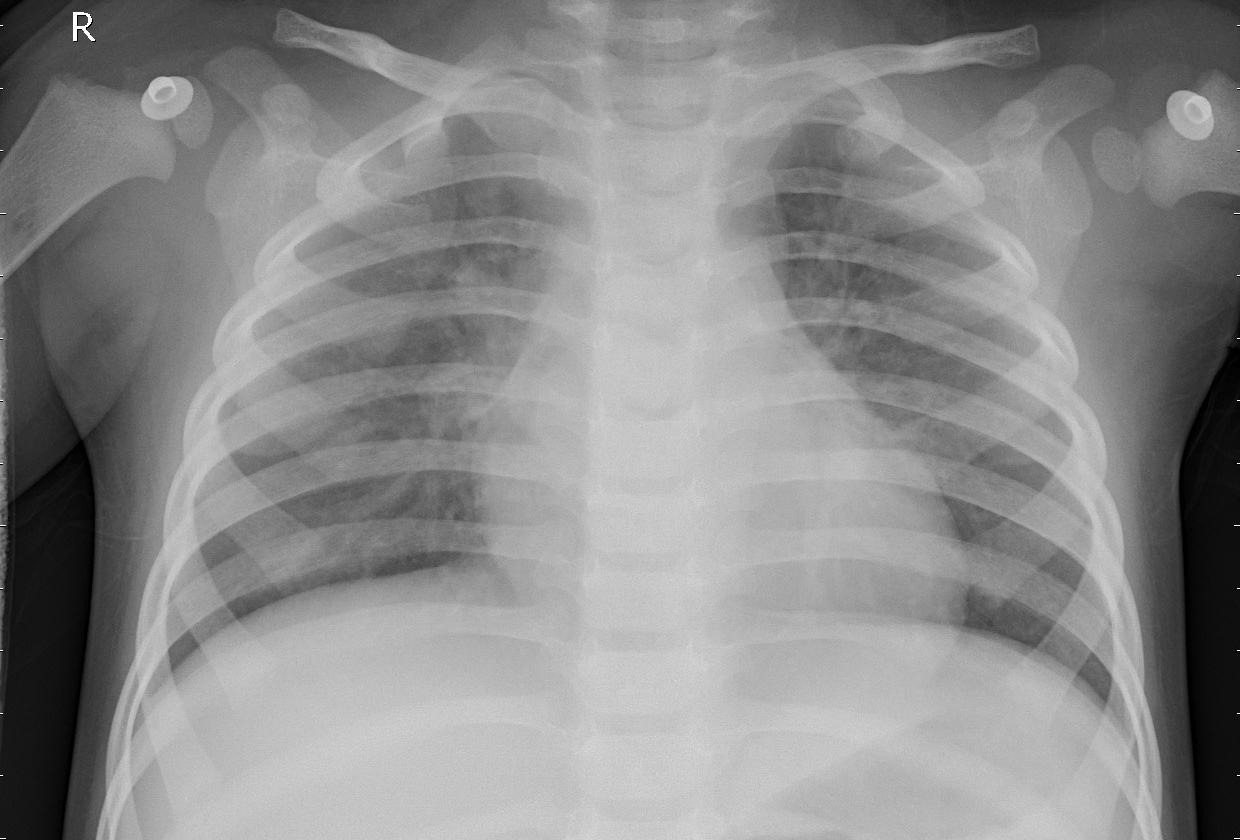

Machine Learning for Medicine - Pneumonia nowadays is still a life-threatening disease that may affect young children's lives. To exam the illness, an X-ray scan is usually taken and the infected area may be detected by doctors. The project aims to develop a program that assists doctors to determine the situation.

Image Classification - X-ray images are processed and input into the program and an output stating whether there is a case of pneumonia will show.